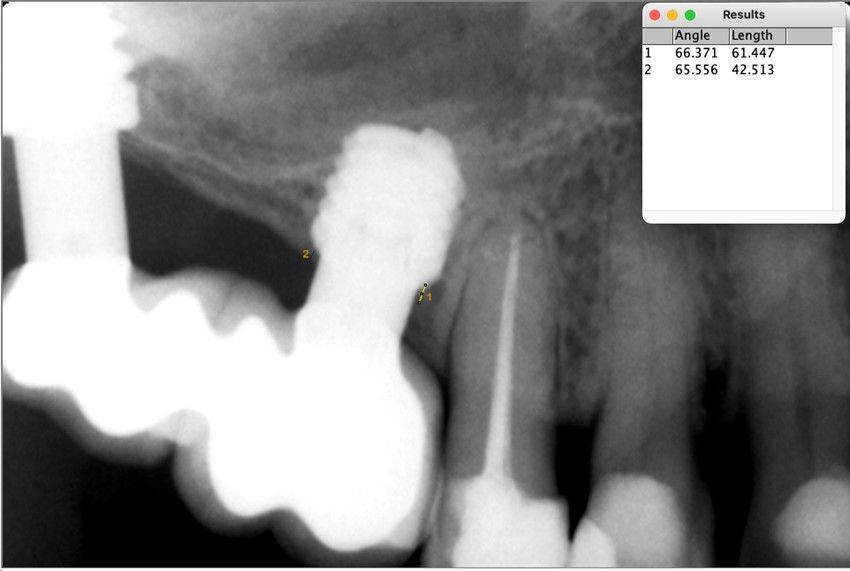

Nuestro grupo de estudio modifica esta técnica de elevación transcrestal utilizando para el acceso unas fresas de corte frontal que permiten eliminar la cortical inferior del seno con lentitud sin dañar la membrana de Schneider, eliminándose los osteotomos y el malestar que genera su accionamiento mediante el martillo6-7. Inicialmente el procedimiento fue concebido para ser empleado con material de injerto al igual que el abordaje convencional, pero posteriormente se presentaron variaciones del procedimiento donde se insertaban los implantes sin injerto, utilizándose el propio implante como mantenedor de espacio entre la membrana de Schneider y la cavidad creada entre la membrana y la cresta, permitiendo que esta cavidad no se colapsase y posteriormente fuera colonizada por nuevo hueso7-11.

Los senos tratados con la técnica de elevación transcrestal sin material de relleno muestran un incremento de entre 2,5 mm12,13 hasta 4.4 mm14,15 en la altura ósea lograda sobre el ápice y una supervivencia de los implantes que se sitúa entre un 94 y un 100%16-17. En este trabajo se presenta un estudio retrospectivo donde se ha evaluado la inserción de implantes extracortos (5,5 y 6,5 mm) en zonas posteriores maxilares mediante la técnica de elevación de seno transcrestal con la fresa de ataque frontal sin la utilización de material de injerto, con un tiempo de seguimiento de 10 años para poder objetivar el comportamiento de los implantes a largo plazo y de la técnica empleada.